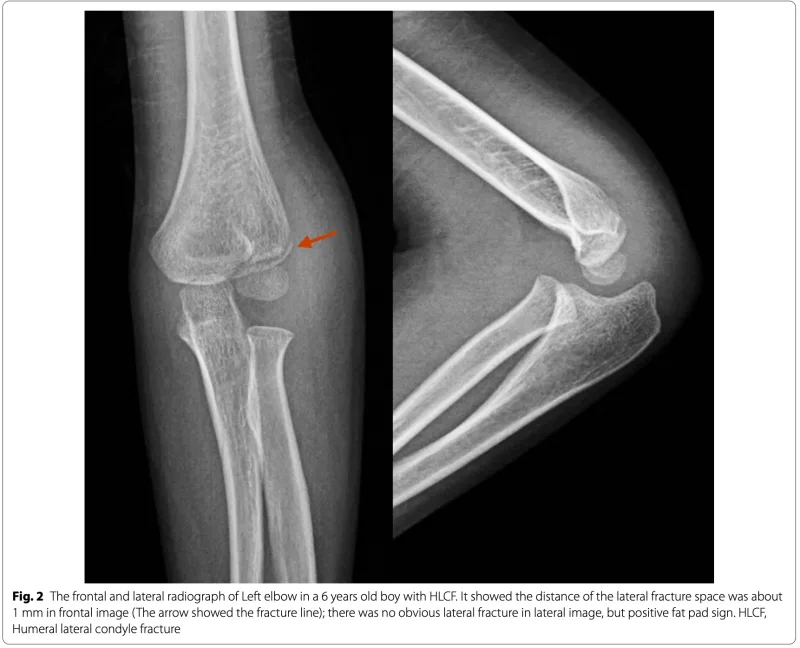

上腕骨外顆骨折の幼児

わずかに→部分で骨が折れているのが判ります.

見逃されやすい骨折なので, 骨折していない側(健側)のX線写真も撮像して, 比較することが必要になることもあります.

2週間前に上腕骨外顆骨折を受傷された4歳の幼児が紹介でこられました.

幸い, ズレはほとんどなかったため ギプスが巻かれていました.

今日は, ギプスをカット.

X線写真では, 骨がつながってきており, ギプスは除去したままとしました.

2週間後に肘関節の動きをチェックして, 終了の予定.